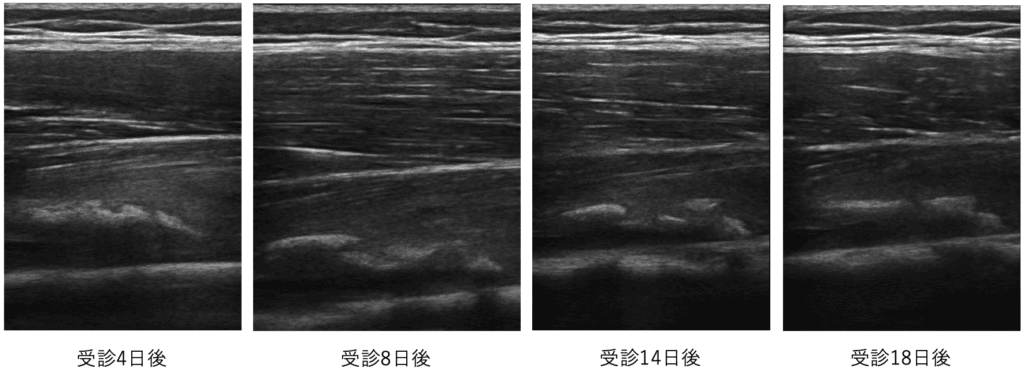

当院受診4日後から18日後までのエコー画像です。石灰像が扁平化してきている事がわかります。

この時点では、圧痛・ストレッチ痛・しゃがみ込みでの痛みがみられています。